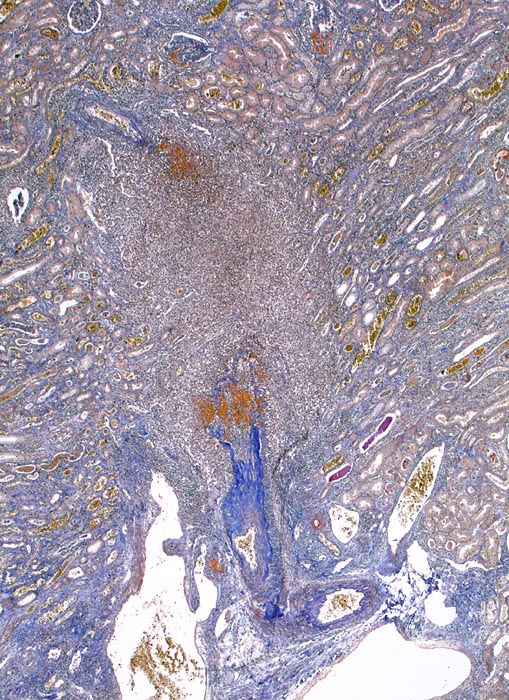

extrakapilläre Glomerulonephritis bei Morbus Wegener

Interlobäre Arterie mit sektorförmiger Nekrose begleitet von einem dichten Entzündungsinfiltrat.

Die Einbeziehung von Endstrecken der afferenten Arteriolen in die glomeruläre Nekrose ist häufig. Eine Vaskulitis der vorgeschalteten Gefässabschnitte wie in diesem Fall ist ungewöhnlich und passt eher zu einer Polyarteritis nodosa Makroform. Bei dieser Erkrankung sind die Glomerula aber definitionsgemäss nicht betroffen.